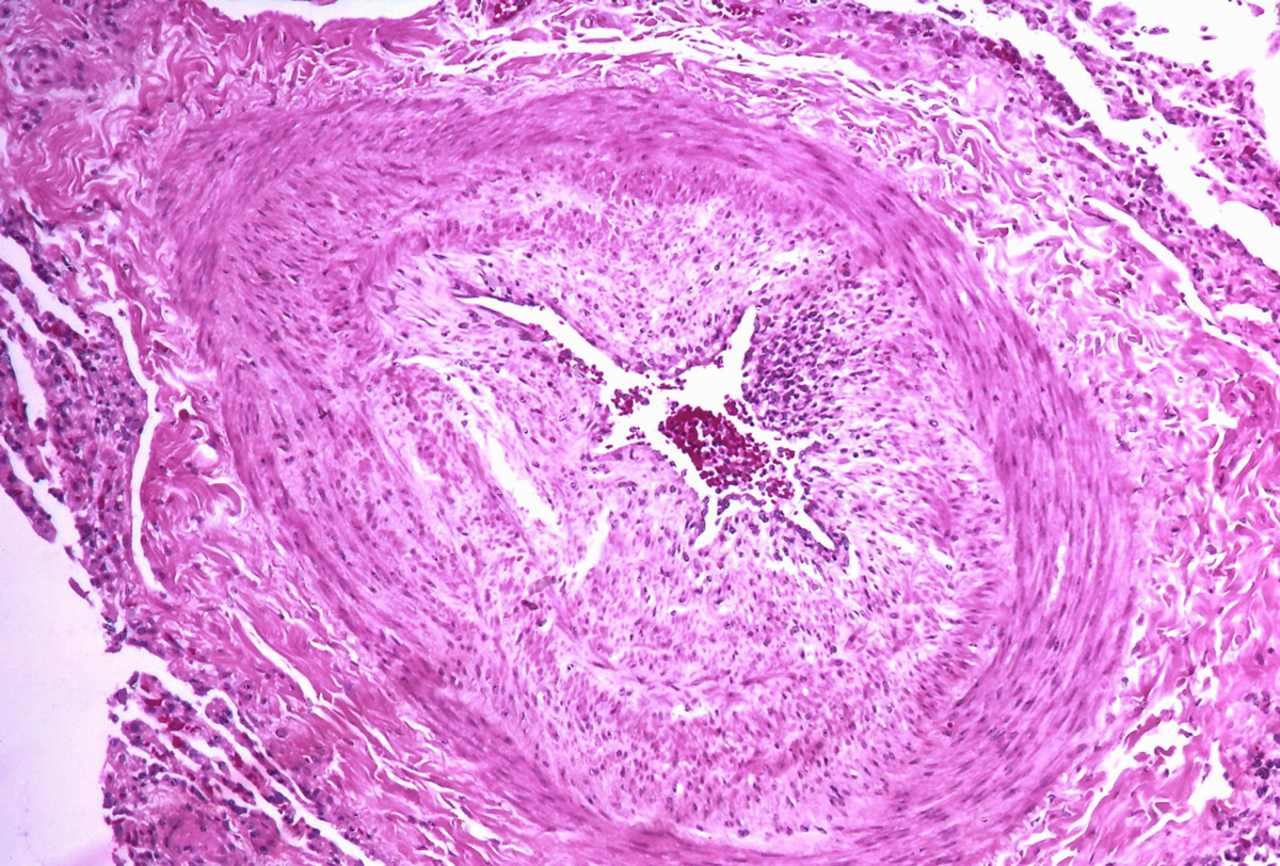

Der bisherige Grenzwert zur pulmonalen Hypertonie könnte sich ändern. Der bisherige Grenzwert zur pulmonalen Hypertonie könnte sich ändern. © Flickr/Yale Rosen (CC BY-SA 2.0)